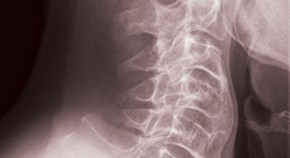

• Lessons from the study of other rheumatic diseases are improving our understanding of diffuse idiopathic skeletal hyperostosis (DISH). New data implicate Dickkopf-1 in the evolution of the most severe manifestations of the condition. Nevertheless, real insights into the pathogenesis—and treatments that might result from them—are still lacking.

• Reuven Mader

• Jorrit-Jan Verlaan

News & Views